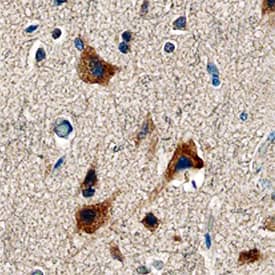

LRG1 antibody in Human Brain by Immunohistochemistry (IHC-P).

LRG1 in Human Brain.

LRG1 was detected in immersion fixed paraffin-embedded sections of human brain (cortex) using Sheep Anti-Human LRG1 Antigen Affinity-purified Polyclonal Antibody (Catalog # AF7890) at 3 µg/mL overnight at 4 °C. Tissue was stained using the Anti-Sheep HRP-DAB Cell & Tissue Staining Kit (brown; Catalog # CTS019) and counterstained with hematoxylin (blue). Specific staining was localized to neurons. View our protocol for Chromogenic IHC Staining of Paraffin-embedded Tissue Sections.